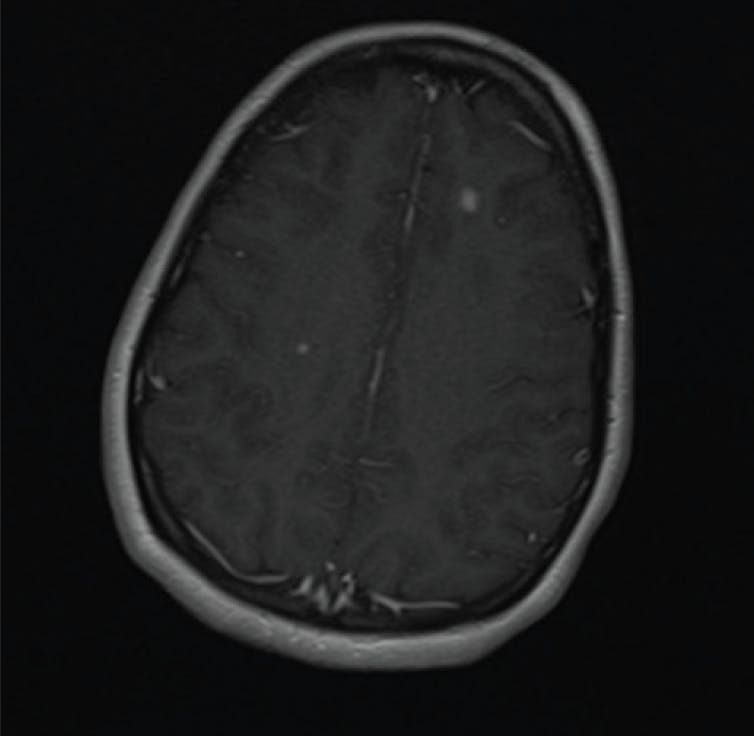

A 39-year-old male presented with symptoms of diplopia when looking to the left. Examination showed a constant left esotropia that corrected with 8 base out prism in the primary gaze and 14 base out in the left gaze. He had a nonconcomitant deviation consistent with a left sixth nerve palsy. MRI revealed “multiple T2 and FLAIR hyperintense lesions in the subcortical and periventricular white matter with a large more conglomerate region of T2 hyperintensity in the left frontal subcortical white matter suspicious for demyelinating disease/multiple sclerosis” (Figure 5). I referred this patient for a neurology consultation, which indeed revealed a diagnosis of multiple sclerosis.

Case No. 4